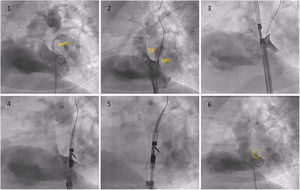

Fluoroscopy sequence of PFO closure with the NobleStitch® EL system. (1) Initial angiography showing contrast passage (yellow arrow) through the PFO. (2) Sizing balloon interrogation during contrast injection of the PFO outlines the septum secundum and septum primum anatomy. After placement of a 0.032́́ wire in the left superior pulmonary vein and a 0.018́́ wire in the superior vena cava, the NobleStitch secundum (3) and primum (4) catheters are sequentially advanced to suture the septum secundum and the septum primum (5), respectively. Contrast may be injected to help optimal engagement of each septum. After each needle firing, the delivery system is removed, providing a long loop of suture through each septum. The delivery system is advanced to release a polypropylene knot (6; yellow circle) at the right side of the interatrial septum and trim the excess thread. SP: septum primum; SS: septum secundum.